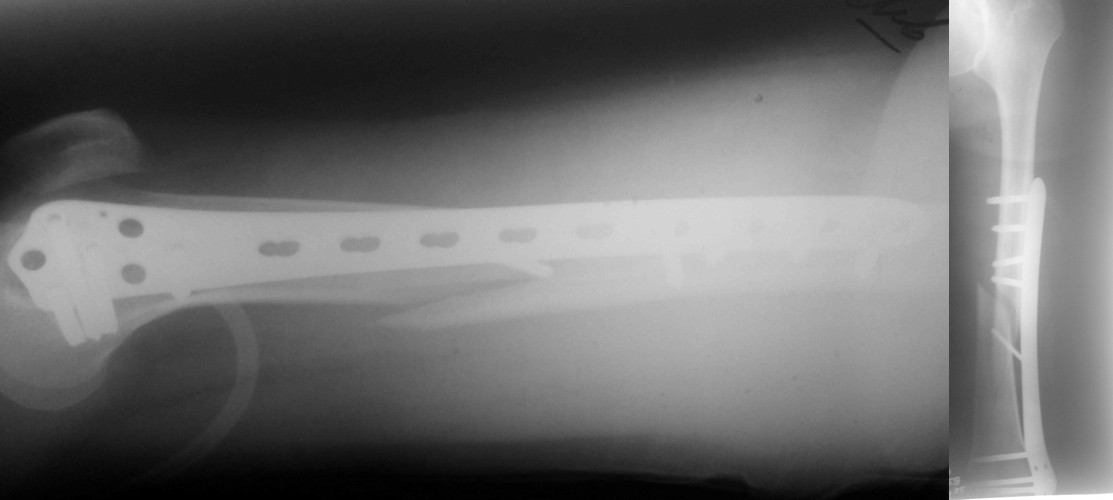

Еще один очень важный нюанс при лечении диафизарных переломов бедра и голени - это лигаментотаксис. Простыми словами, перелом нужно достаточно растянуть. Нам известно три способа как это сделать:

1) мануальный руками (самый дешевый и распостраненный, требует недюжинных усилий и +1 ассистента)

2) ортопедический стол (самый дорогой, длительное время на подготовку)

3) большой бедренный дистрактор (самый любимый, золотая середина)

В данному случае, в том числе, перелом не был достаточно растянут. Во многих случаях (преимущественно все-таки при многооскольчатых переломах) именно тракция является основным репонирующим моментом, который и восстанавливает длину и ось. Остается только следить за ротацией. Мышечно-фасциальные футляры во время тракции восстановят правильные соотнешения, если только нет интерпозиции.

Представляю вам один из наших недавних случаев выполнения малоинвазивного остеосинтеза бедренной кости обычной пластиной 95 градусов. Длина восстановлена с помощью дистрактора (по сути это основная и б(о)льшая часть репозиции). Произведено два небольших доступа, проведена спица направитель. Рентген-контроль для подтверждения достаточной длины/оси (ЭОП использовался в другой операционной). Создание туннеля обратной стороной фиксатора. Поворот фиксатора, введение клинка по спице. Фиксация проксимального и дистального концов пластины.